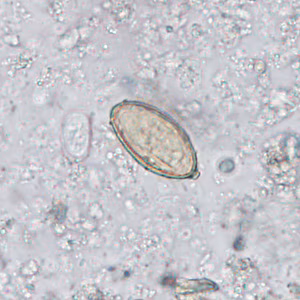

2015 DPDx Case Studies

DPDx Case Studies – 2015

DPDx is an educational resource designed for health professionals and laboratory scientists. For an overview including prevention, control, and treatment visit www.cdc.gov/parasites/.